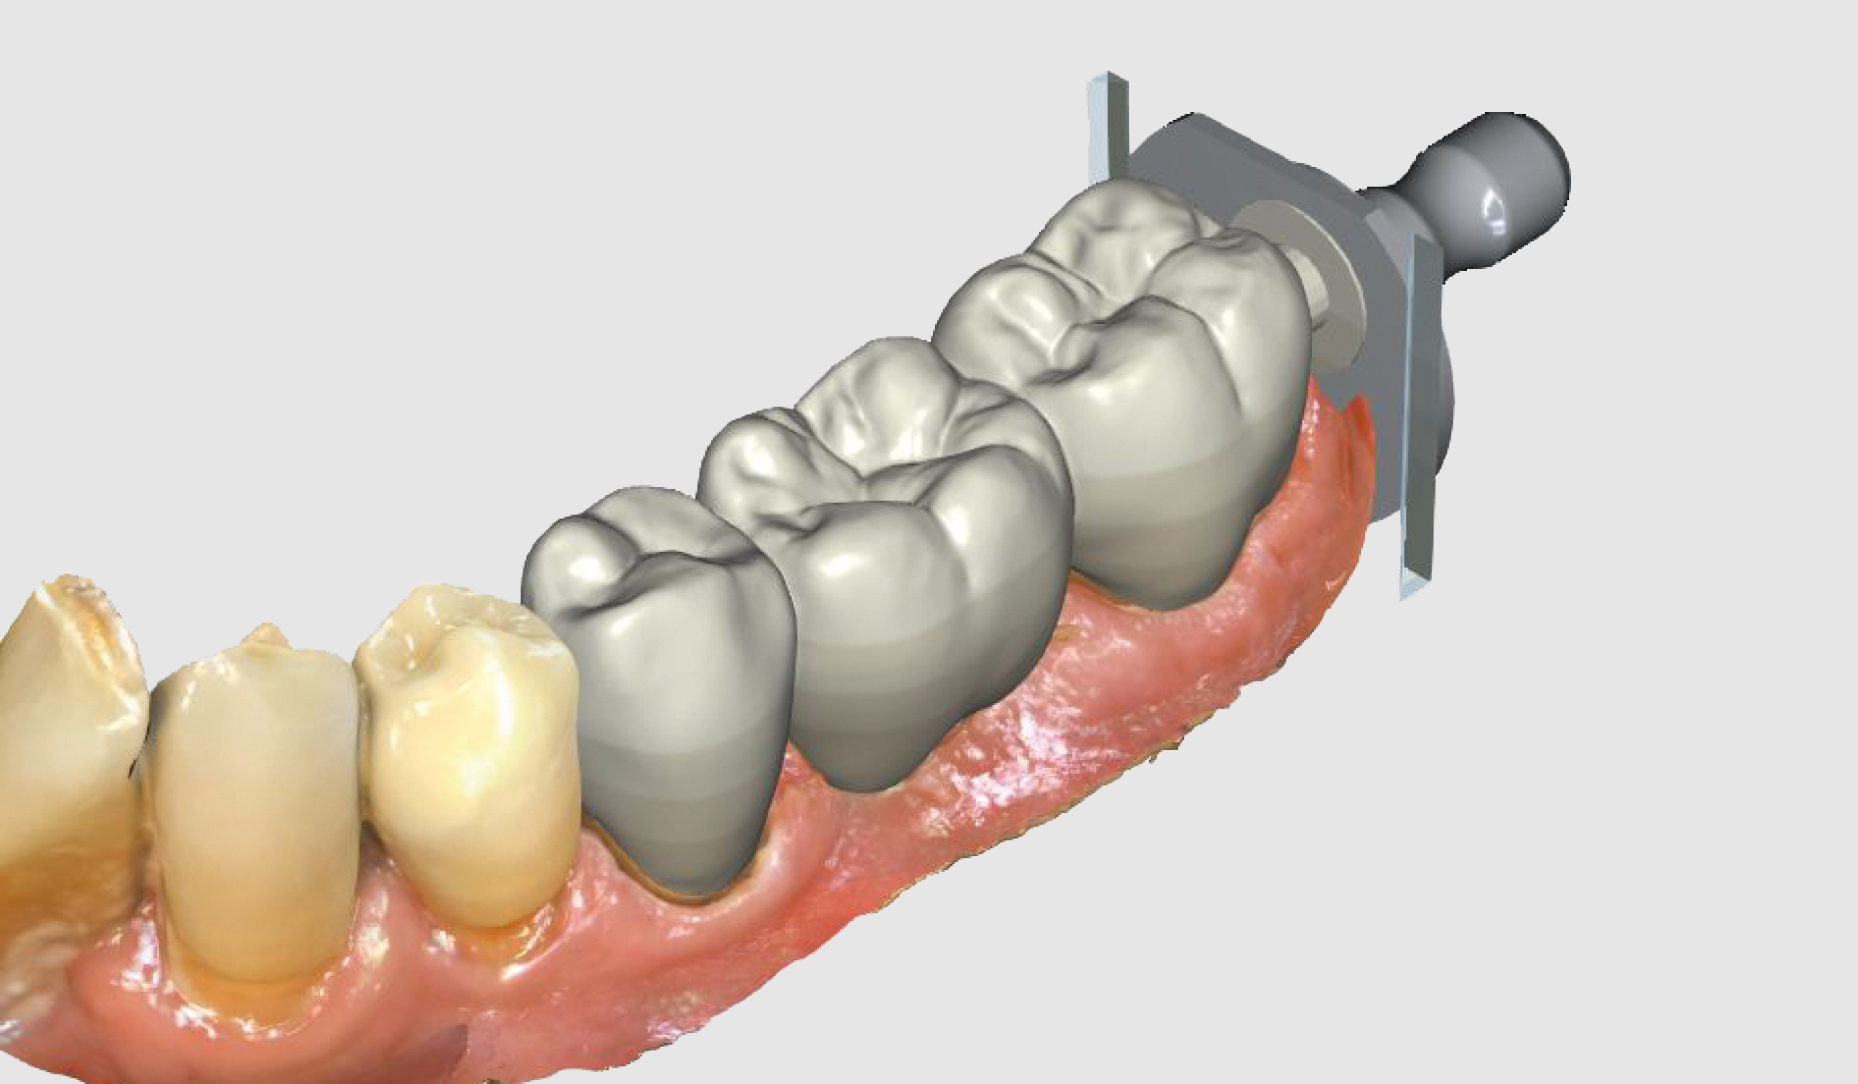

Ryc. 4. Projekt mostu...

Ryc. 5. ...widok powierzchni żującej w oprogramowaniu CEREC.